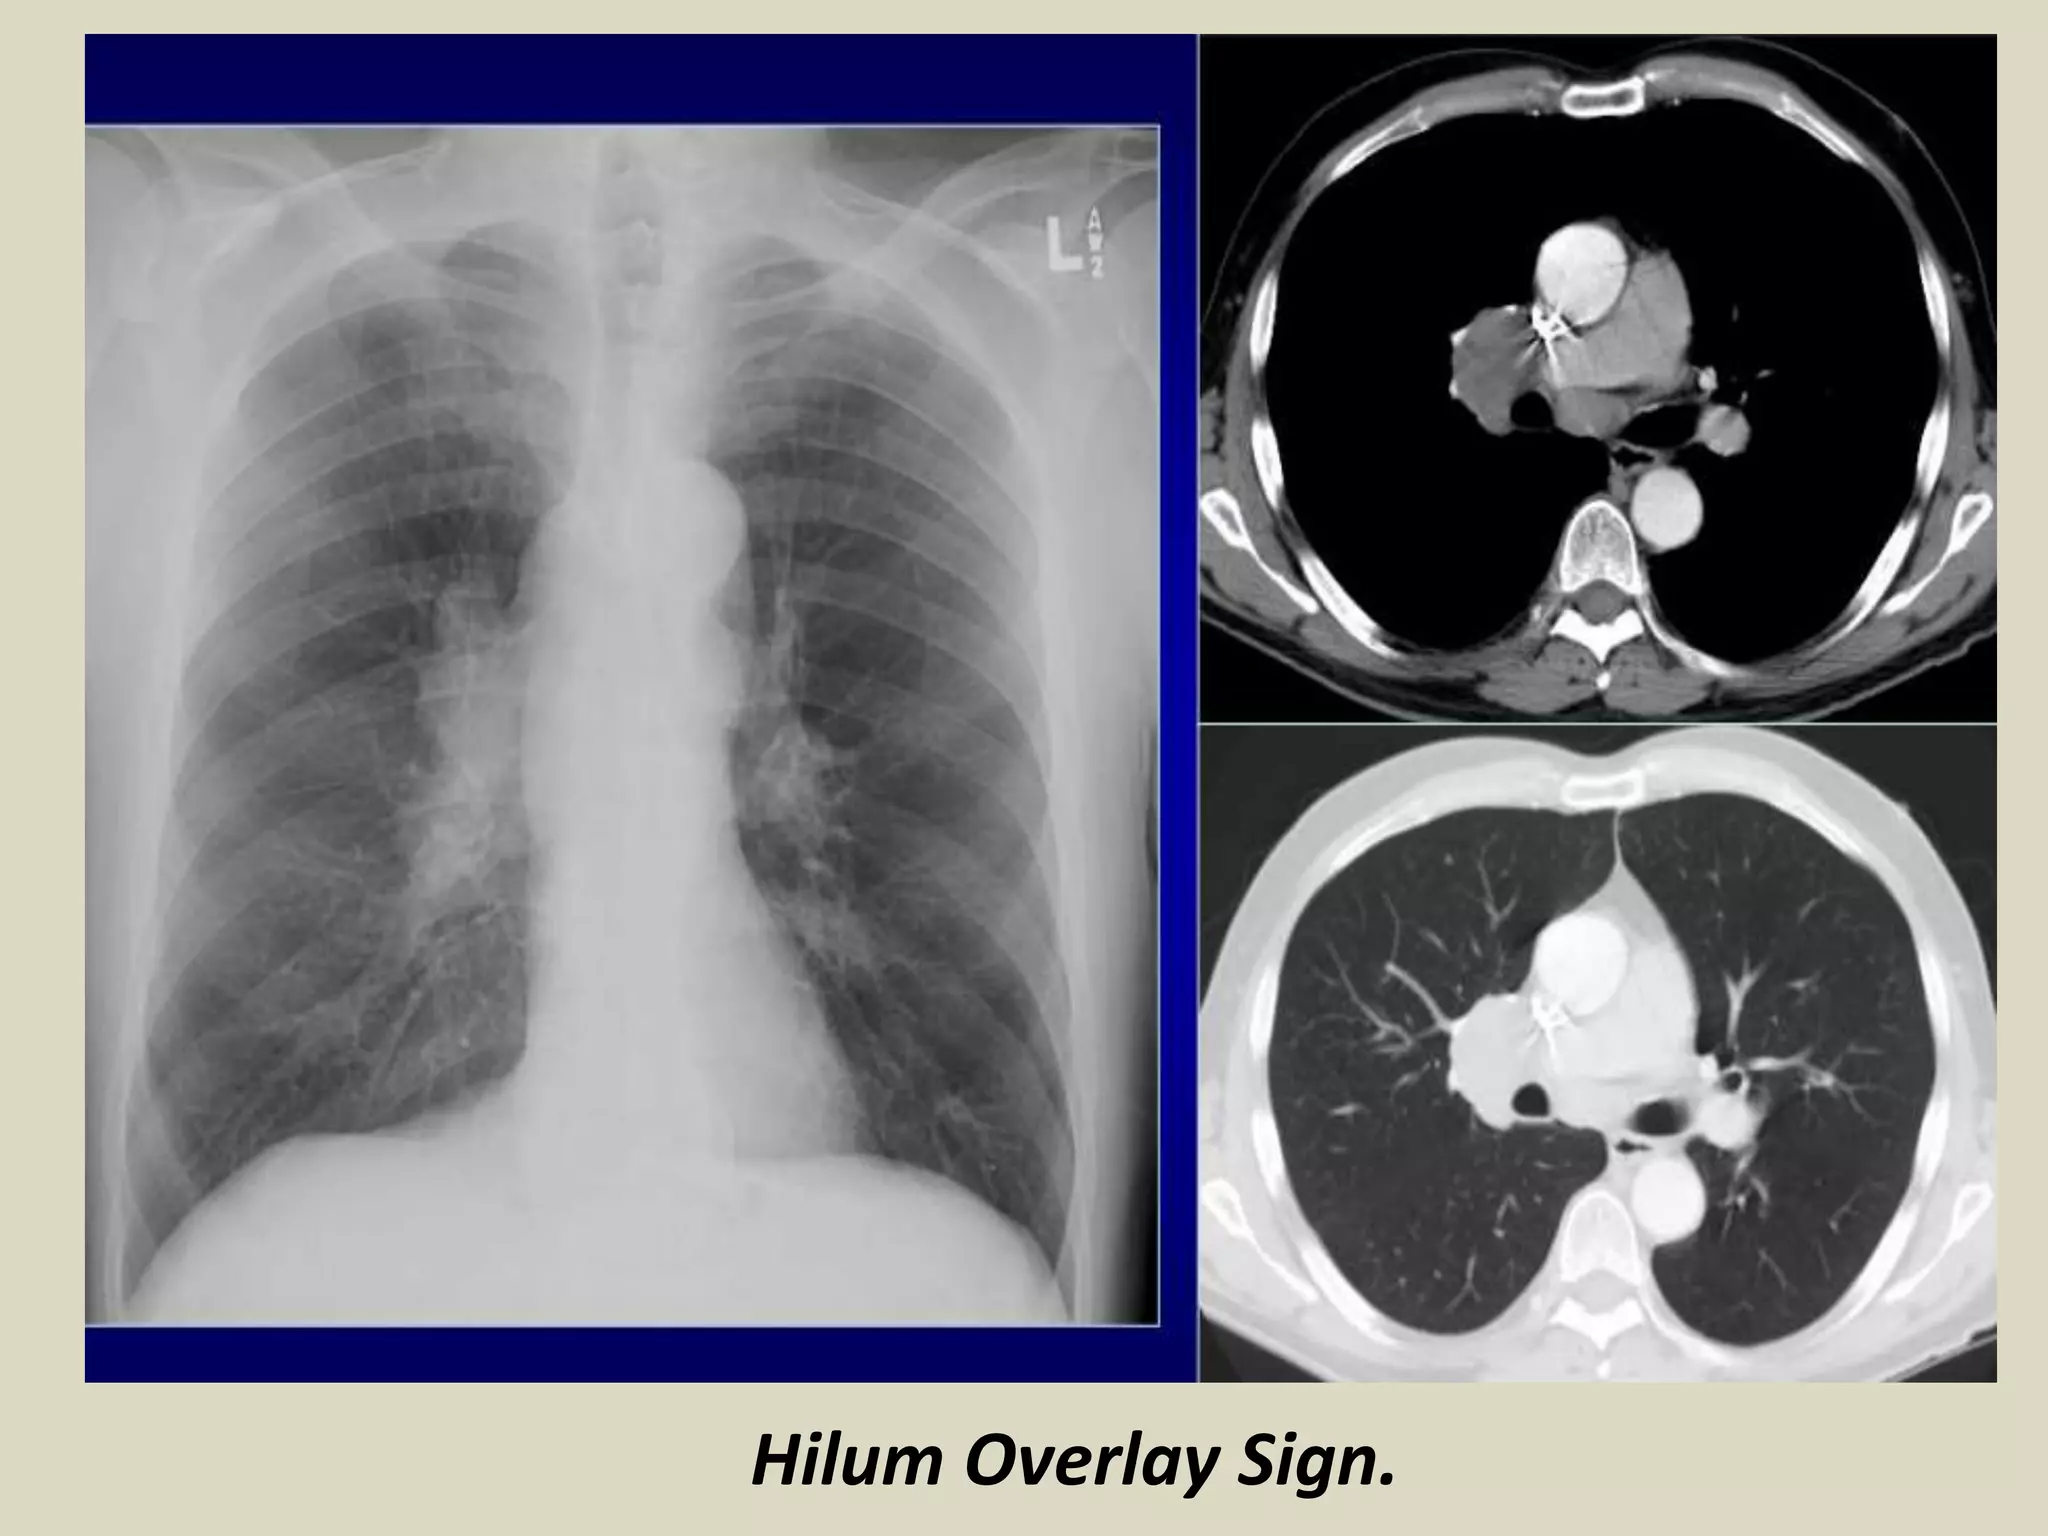

HILUM OVERLAY SIGN

Described by Benjamin Felson

If hilar vessels are sharply delineated it can be assumed that the overlying mass is

anterior or posterior

If mass is inseparable from pulmonary arteries, structures are adjacent to one

another

HILUM OVERLAY SIGN. Chest radiograph with schematic drawing.

• Described by B. Felson

• If hilar vessels are sharply delineated it can be assumed that the overlying

mass is anterior or posterior

• If mass inseparable pulmonary arteries structures are adjacent to one another

Hilum Overlay Sign.